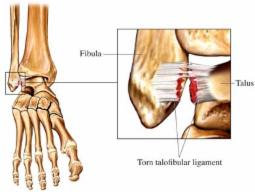

| - NUEVO APARTADO EN LA WEB: "LESIONES". - Para acceder ha este apartado bien puede hacer click en el enlace: |